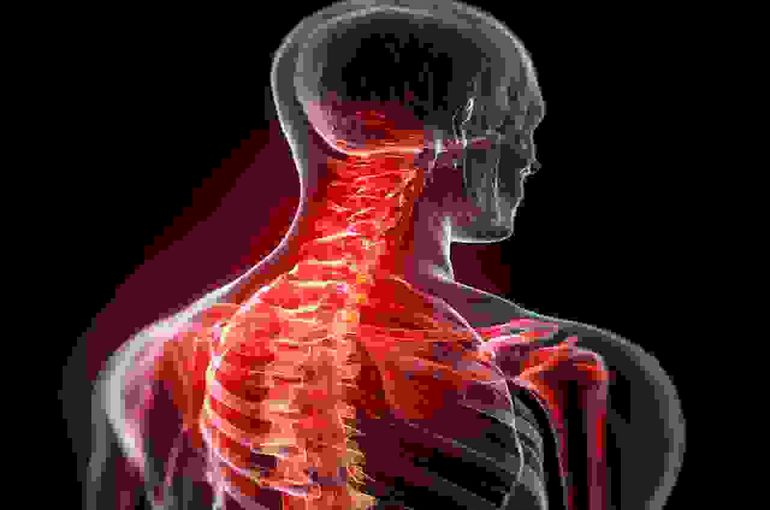

この状態が長時間続くと、首の後ろ側の筋肉は常に引き伸ばされ、前側の筋肉は縮こまって硬くなります。結果として、本来ゆるやかなS字カーブを描いているべき頸椎が、徐々にまっすぐな状態へと変化し、ストレートネックが形成されてしまうのです。

このような姿勢は、肩や首の筋肉を常に緊張させ、血行不良を引き起こし、さらには猫背を誘発します。猫背は、首の自然なカーブを失わせるだけでなく、全身のバランスを崩し、ストレートネックをさらに悪化させる要因となります。

この状態が長期間続くと、筋肉は慢性的な緊張状態に陥り、柔軟性を失います。硬くなった筋肉は、首の骨(頸椎)を引っ張り、その結果、頸椎の生理的なS字カーブが失われ、ストレートネックを引き起こしたり、悪化させたりする原因となります。